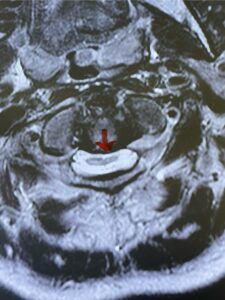

This is a 42 year-old female who presents with severe progressive weakness and numbness and difficulty with balance over a 6-month period. She has a history of having a motor vehicle accident at 5 years old but was never imaged. On exam she was noted to be severely myelopathic. Imaging revealed severe spinal cord compression at the level of C1 (Figs 4a and b).

Fig. 4b: Axial T2-weighted cervical MRI demonstrating severe spinal cord compression from atlanto-axial instability (red arrow)